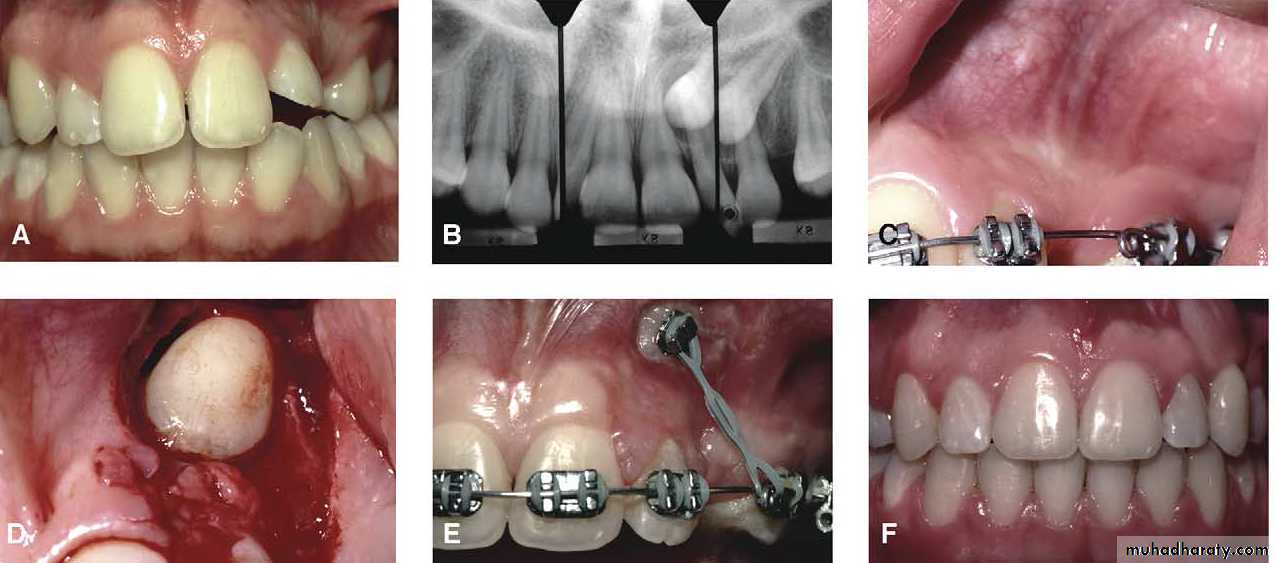

Surgical exposure with orthodontic treatment (palatal approach )

Following eruption of the tooth , orthodontic treatment may be required to guide it into a good position in the arch . Some times orthodontic traction is arranged at the time of surgery .

The initial stage of the operation is to reflect the mucoperiosteum and to remove the bone overlying the tooth to expose the greatest coronal diameter, the incisal edge and the cingulum . before repositioning the palatal flap a window is excised in it corresponding to the bony cavity containing the crown .the flap is then sutured as usual and a pack of iodoform gauze should be pressed firmly in to the bony defect so as to cover the exposed crown .

Mosul university- College of dentistry-oral & maxillofacial surgery department

This pack should be held in position with suture and left insitu for 2-3 weeks to prevent granulation tissue and mucosa from overgrowing the denuded crown .after removal of the pack the progress of eruption should be observed at frequent intervals .